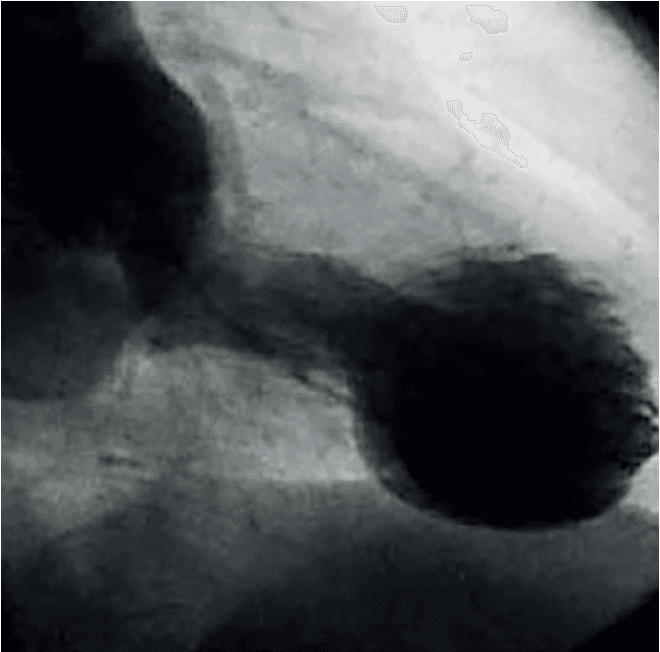

A incidência de trombos no ventrículo esquerdo (VE) após infarto agudo do miocárdio (IAM) diminuiu nas últimas décadas devido aos avanços nas técnicas de reperfusão e terapias antitrombóticas. Apesar …

Como já havíamos discutido previamente (aqui e aqui), não existem ensaios clínicos randomizados de grande porte sobre os benefícios de anticoagulação oral em pacientes com trombo de ventrículo esquerd…